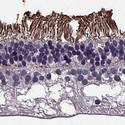

voltagegated_CACNA1_in retina.jpg

Ion channels are pore-forming membrane proteins that selectively facilitate the rapid, passive movement of specific ions across various cell membranes and play an important role in many of our organ systems. In the Human Protein Atlas, the voltage-gated ion channels are represented by more than 100 genes from nine different subcategories based on their selectivity and the ions they conduct...Read more